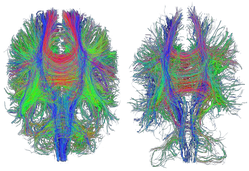

Concussion injury on a microscopic scale

As you may recall from earlier blogs, mTBI involves damage on a microscopic scale. This is often too small to be visible on brain scans. Researchers working in the CENTER-TBI group are working hard to clarify as much and as soon as possible.